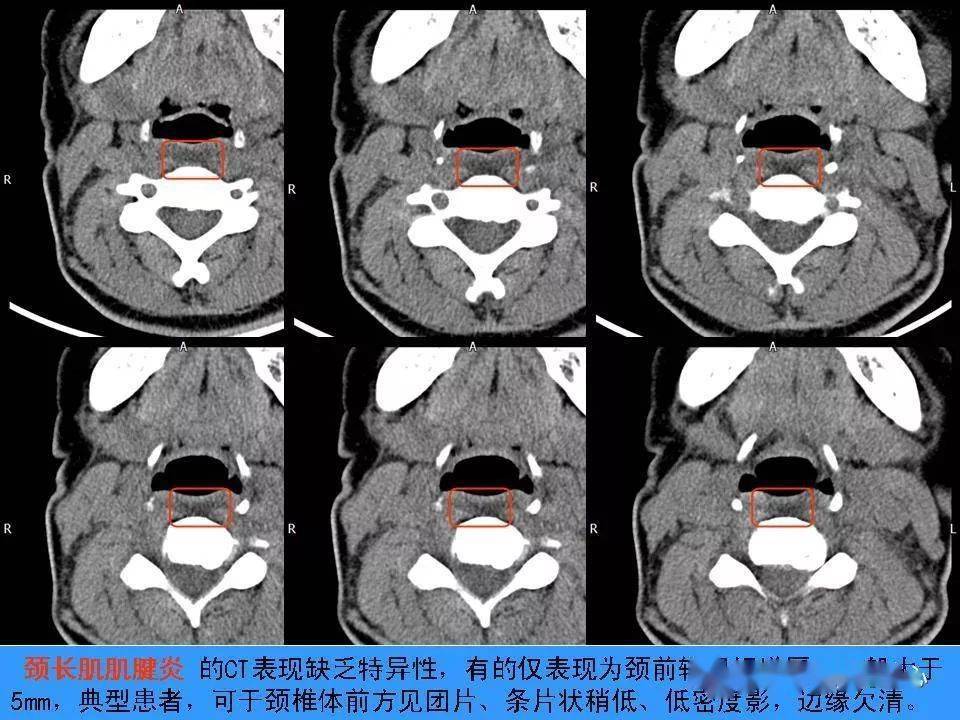

颈椎骨性异常表现

图片尺寸1080x1440